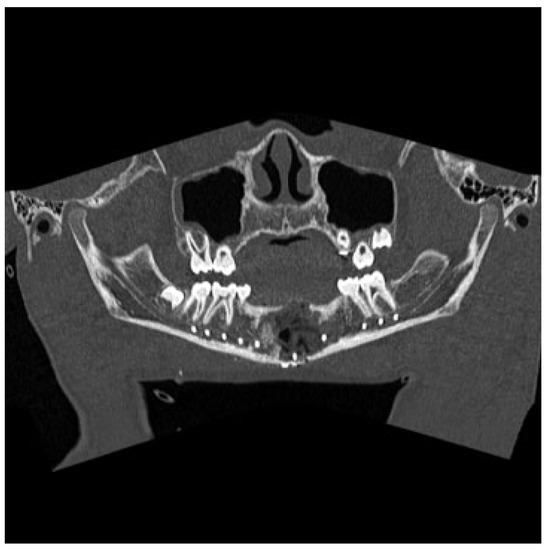

Figure 6.

Panorex computed tomography scan obtained 1 year postoperatively demonstrating near-complete ossification of the cys- tic defect of the mandible.